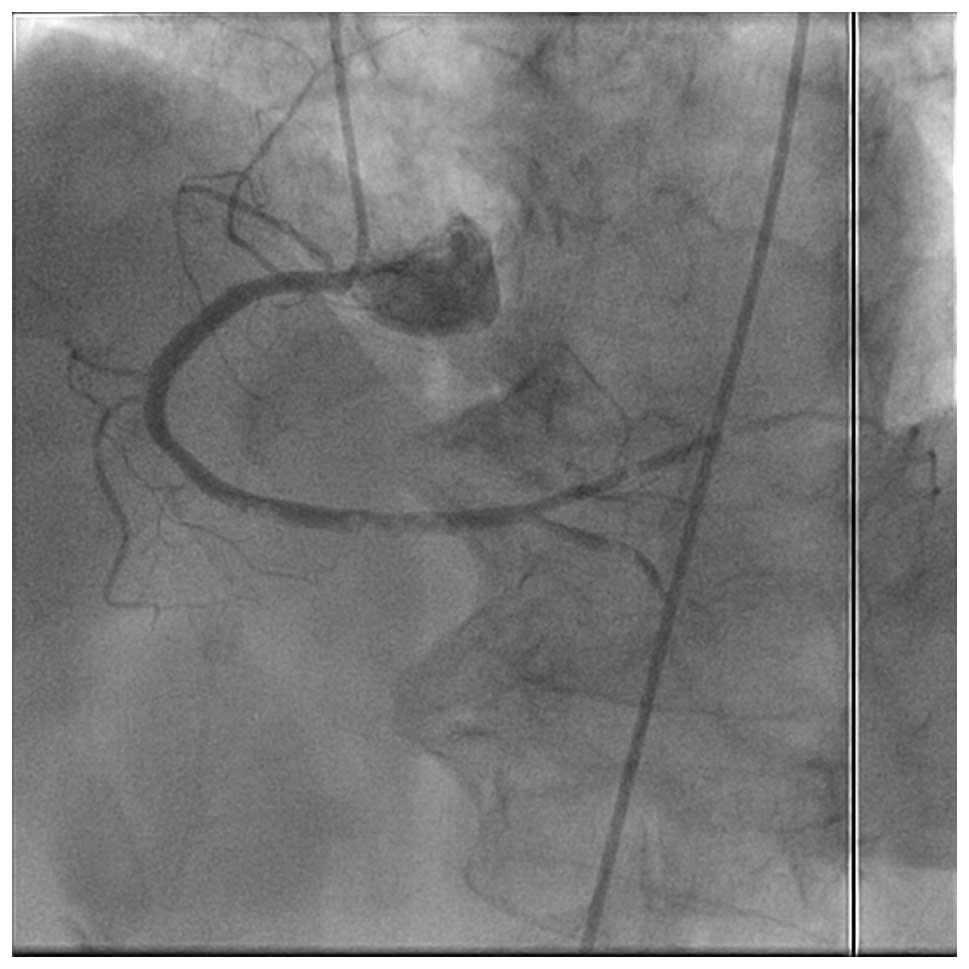

A 65-year-old female with stable angina was scheduled to undergo follow-up for coronary angiography 9 months after the performance of an index procedure. According to the routine procedure, a standard JL4 diagnostic catheter via the right femoral artery was employed to catheterize the left coronary artery. On engagement and initial injection of the left coronary artery, the patient began to experience severe chest pain and the ST segment in leads II and III began to rise. Immediately, the catheter was exchanged and right coronary artery angiography was performed. Multiple small bead-like shadow defects suspected to be air bubbles were present in the mid-portion of the right coronary artery and interruption of blood flow was observed (Fig. 1). The patient went into a shock state with complete atrioventricular block and hypotension. Immediately, the patient received 100% oxygen inhalation through a facemask. Contrast dye was forcefully injected several times and the air bubbles dispersed distally (Fig. 2). The treatments were successful in terms of improvement in the condition of the patient. Subsequently, the patient recovered from the state of shock. Later, angiography confirmed the disappearance of air embolism and sufficient blood flow was obtained in the right coronary artery. The patient had an uneventful overnight stay and was discharged the following day with a normal electrocardiogram (ECG) and cardiac enzyme levels. Written informed consent was obtained from the patient.

Figure 1

Right coronary artery immediately after left coronary angiography. A massive air embolism interrupted the blood flow in the mid-portion of the right coronary artery.

Figure 2

Right coronary angiogram immediately after left coronary angiography. Small shadow defects were considered to be air bubbles present in the distal portion of the right coronary artery and later the bubbles dispersed distally.